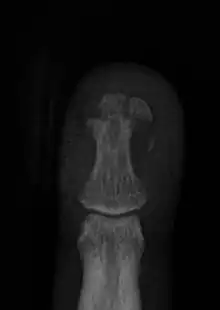

| Dorsal hand injury seen in a child | |

Finger injuries are usually diagnosed with x-ray and can get to be considerably painful. The majority of finger injuries can be dealt with conservative care and splints. However, if the bone presents an abnormal angularity or if it is displaced, one may need surgery and pins to hold the bones in place.